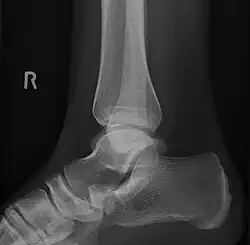

Lateral projection of type 2 -

Type 2 -